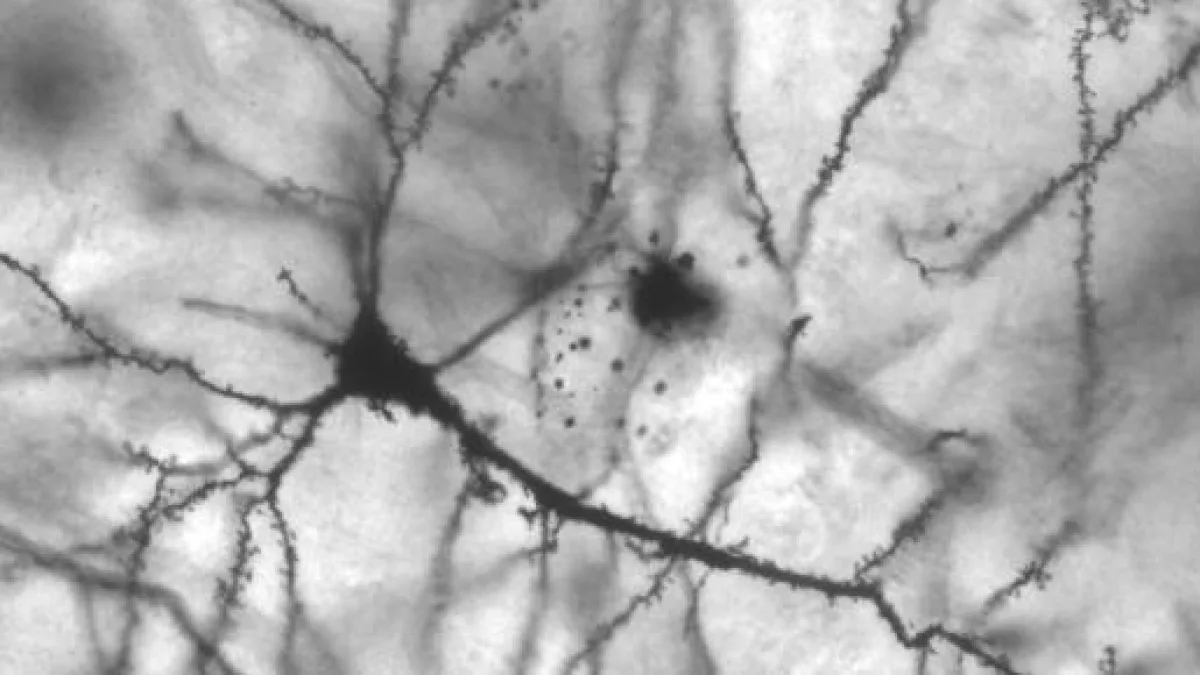

Cuando el cerebro recibe información sensorial, la actividad neuronal genera unos patrones determinados. Según ciertas investigaciones, para que exista la consciencia, es necesario que los patrones neuronales que se forman ante cada percepción se mantengan estables durante algunos cientos de milisegundos.

Cuando confirmaban haber visto la imagen, el escáner mostraba que la actividad cerebral se estabilizaba. Cuando decían no haber visto nada, la actividad cerebral era variable. Ahora, con la nueva tecnología, Schurger y su equipo han podido estudiar los campos electromagnéticos generados por el cerebro, lo que les ha permitido estudiar con mayor precisión la formación de patrones neuronales y su desvanecimiento.

En el nuevo experimento, se ha observado la actividad cerebral de 116 personas con trastornos de la consciencia, desde estados vegetativos a pacientes recién salidos de un coma o mínimamente conscientes. Los resultados muestran que la estabilidad de los patrones cerebrales tras una percepción dura más cuanto más consciente es la persona.

La investigación de Schurger proporciona nuevos datos empíricos que muestra que, para que la consciencia sea posible, es necesario que las diferentes áreas del cerebro permanezcan sincronizadas durante algunas centésimas de milisegundo antes de romperse el patrón.